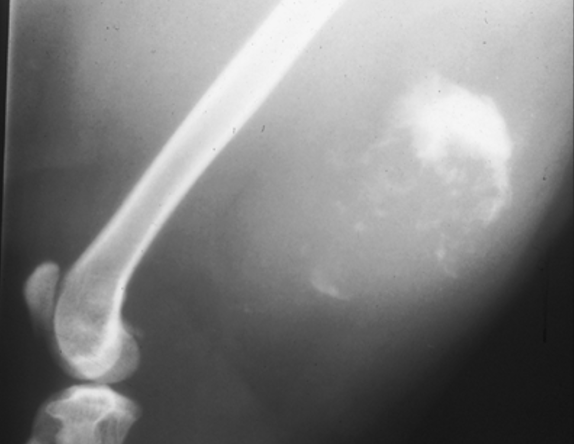

17

Q

What is shown in this radiograph?

A

extra-skeletal osteosarcoma producing bone